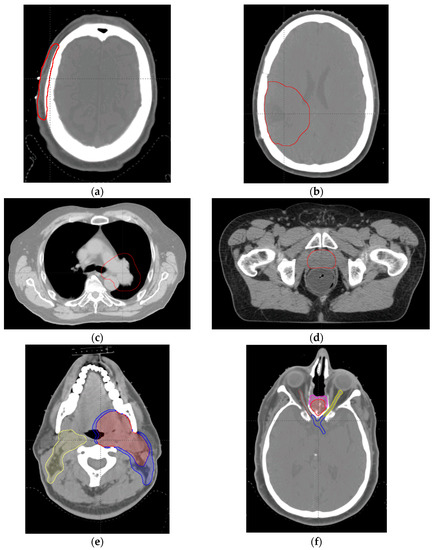

| Case | Target Volume (cc) | Number of Beams | Optimization Method | Prescription (Gy (RBE)/Fraction) |

|---|---|---|---|---|

| Scalp | CTV, 47.3 | 2 | SFO | 48/24 |

| Brain | CTV, 132.7 | 3 | SFO | 50.4/28 |

| Lung | CTV, 582 | 3 | MFO | 66/33 |

| Prostate | CTV, 88.8 | 2 | SFO | 78/39 |

| H & N | CTV1, 161.0 | 3 | MFO | 70/30 |

| CTV2, 83.5 | 63/30 | |||

| CTV3, 225.1 | 57/30 | |||

| BOS | CTV1, 142.0 | 3 | MFO | 70/30 |

| CTV2, 42.5 | 63/30 |